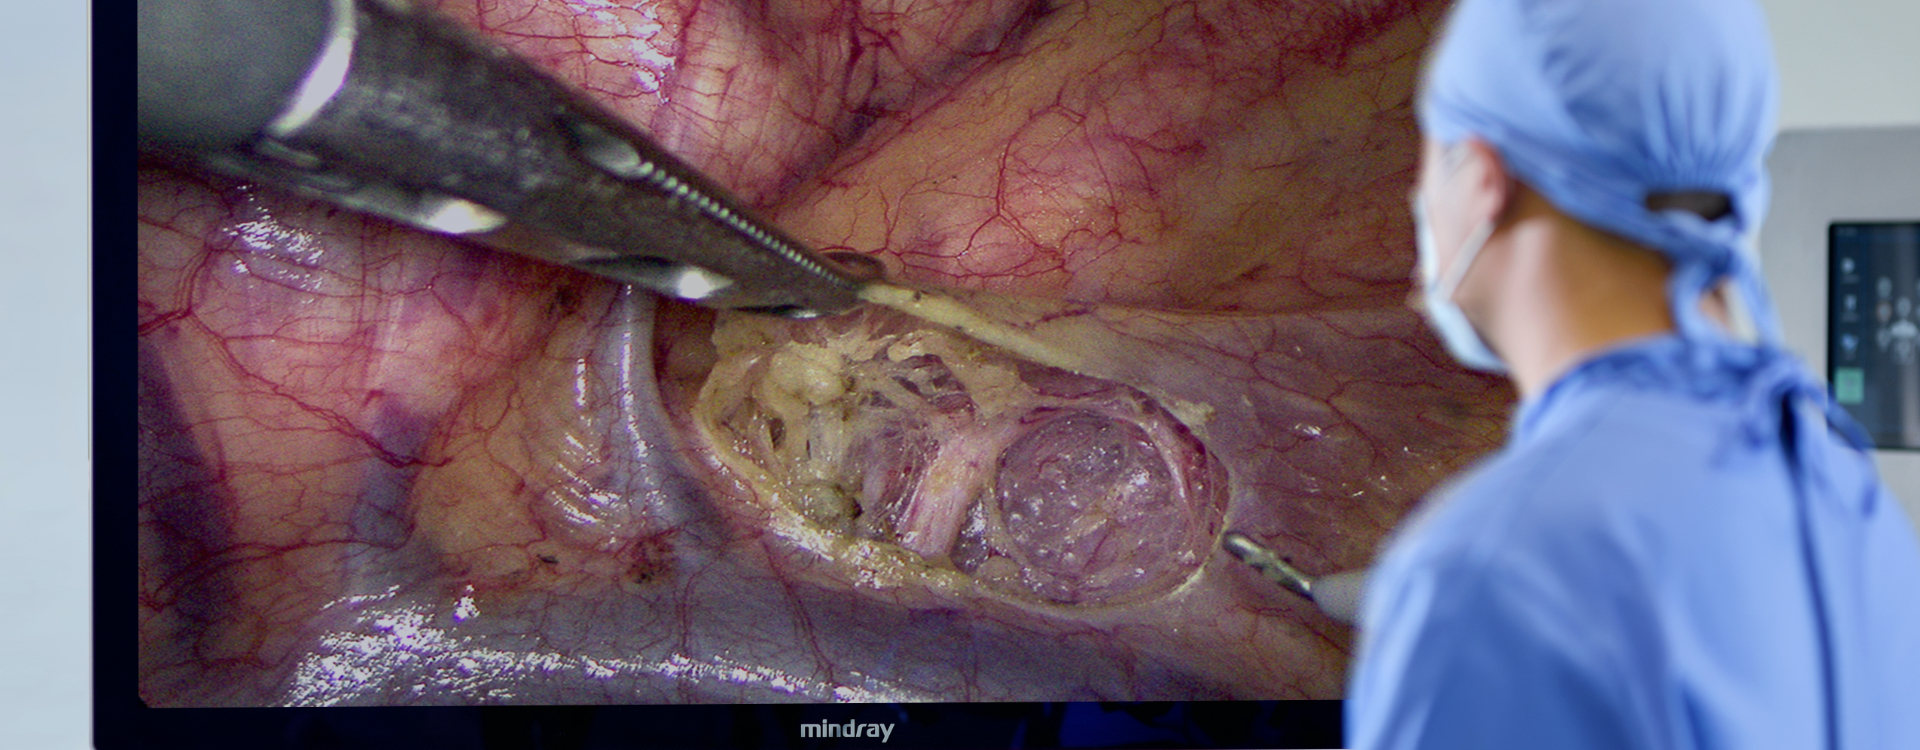

Simply Clear

4K Ultra HD

55 inch Immersive Experience

The surgical image is enlarged without reducing the resolution, so that the details are no longer small, and the doctor’s visual fatigue is reduced.